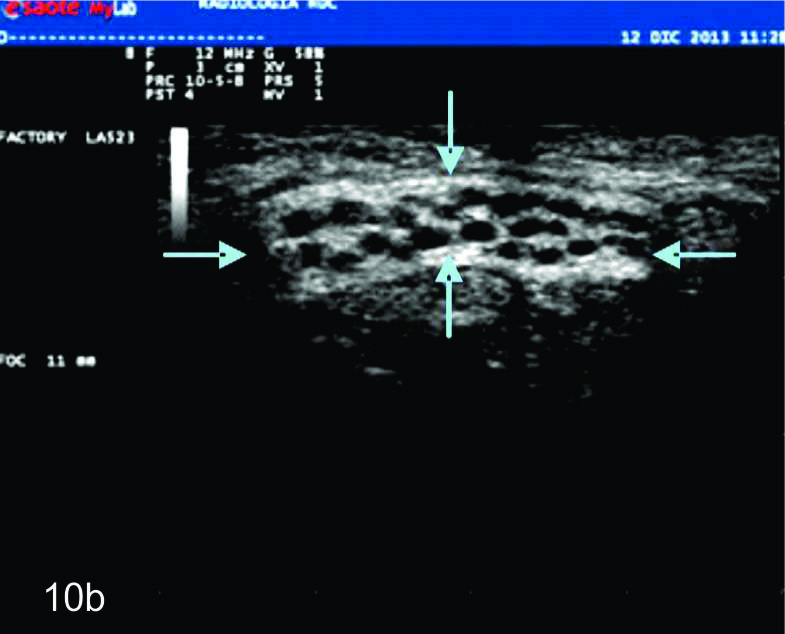

Dada las características ultrasonográficas normales de los nervios, algunas variantes anatómicas pueden ser reconocidas por este método. Entre ellas la bifurcación proximal del mediano en el puño es una de las más frecuentes. De manera similar algunas anomalías heredables y del desarrollo del sistema nervioso periférico, como el agrandamiento fusiforme del nervio mediano por tejido fibroadiposo (denominado hamartoma fibrolipomatoso (Fig.10), la hipertrofia de los nervios en el síndrome de Charcot-Marie-Tooth y el aumento de los nervios en la neuropatía hereditaria secundaria a parálisis por compresiones pueden ser reconocidas por ultrasonido. En estas enfermedades, los hallazgos ultrasonográficos pueden contribuir a la comprensión de la fisiopatología demostrando de forma no invasiva algunos hallazgos morfológicos de interés (1).

Figura 10

Hamartoma fibrolipomatoso del nervio mediano

A y B, cortes transversales en antebrazo y puño, las flechas azules señalan al nervio mediano aumentado de tamaño con fascículos engrosados. C- Corte longitudinal con hallazgos similares en plano longitudinal del nervio (flechas azules).